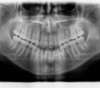

Béance traitée par gouttières

Début du traitement